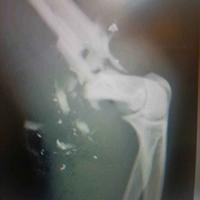

肩关节前脱位伴明显的Hill Sachs

肩关节前脱位伴明显的Hill Sachs....

由 medjpg 发表于 2026-03-24 22:32